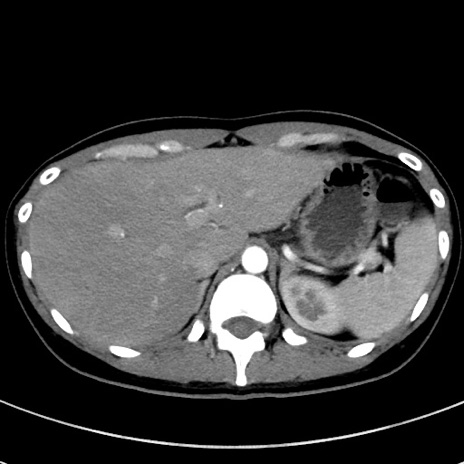

症例17(横断像)

【症例】20歳代女性

【主訴】嘔吐、下腹部痛

【現病歴】昨日夕食後に嘔吐し下腹部痛が出現。本日になっても嘔吐持続し改善しないため来院。

【身体所見】意識清明、BT 37.2℃、BP 108/67mmHg、腹部:平坦、やや硬、下腹部正中から右にかけて圧痛あり、反跳痛軽度あり、tapping pain(+)。

【データ】WBC 13600、CRP 14.94